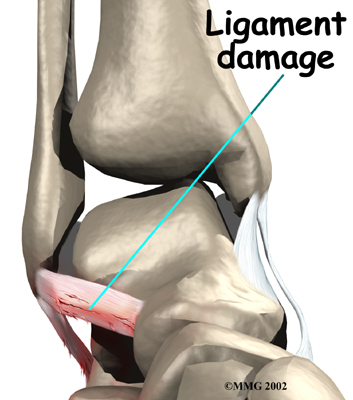

Initially the ankle is swollen, painful, and may turn ecchymotic (bruised). The bruising and swelling are due to ruptured blood vessels from the . Most of the initial swelling is actually bleeding into the surrounding tissues. The ankle swells as extra fluid continues to leak into the tissues over the 24 hours following the sprain.

Initially the ankle is swollen, painful, and may turn ecchymotic (bruised). The bruising and swelling are due to ruptured blood vessels from the . Most of the initial swelling is actually bleeding into the surrounding tissues. The ankle swells as extra fluid continues to leak into the tissues over the 24 hours following the sprain.

Initially the ankle is swollen, painful, and may turn ecchymotic (bruised). The bruising and swelling are due to ruptured blood vessels from the

Initially the ankle is swollen, painful, and may turn ecchymotic (bruised). The bruising and swelling are due to ruptured blood vessels from the